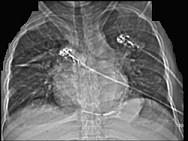

问题 男性45岁,心悸气促乏力,下肢肿胀半年余,曾患肺结核,胸部CT扫描如图所示,请选择正确的选项为 ( )

选项 A、X线、CT为常用检查方法 B、MRI显示增厚的心包较X线、CT优越,但是对心包钙化不敏感 C、心包钙化显著时也可称之为“盔甲心” D、心包钙化多见于结核 E、考虑为缩窄性心包炎 一、多项选择题

答案 ABCDE